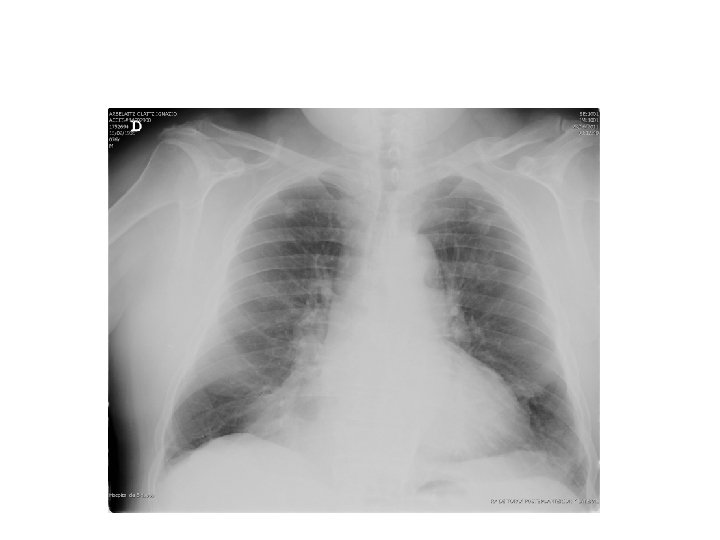

Centrada: claviculas equidistantes Inspirada: 10 arcos posteriores ¿ ESTÁ BIEN SISTEMA DE HECHA LECTURA? Penetrada: vasos y vertebras retrocardicacos TENER EN CUENTA LA POSICION DEL PACIENTE

Senos costodiafragmaticos libres SISTEMA DE LECTURA 3. diafragmaticas Diafragma Cupulas centradas El derecho ligeramente por encima

Tener en cuenta: Similar TAMAÑO SISTEMA DE LECTURA 5. Hilios pulmonares Similar DENSIDAD Hilio IZQUIERDO SUPERIOR

Arterias y venas Lineas que DE llegan LECTURA a la periferia SISTEMA 6. Estructuras vasculares Bifurcadas en angulo agudo Grosor disminuye hacia la periferia Más marcado en bases

SISTEMA DE LECTURA 6. Silueta Estructuras cardiovasculares Indice cardiotorácico